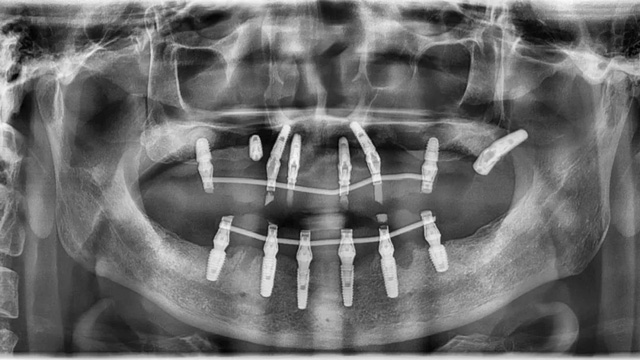

王先生的口腔全景片(2021年9月/新橋口腔成都玉雙院區(qū))

接診王先生的是新橋口腔成都衣冠廟院區(qū)種植專科主任李陽軍,“我們在系統(tǒng)里查到了他之前的就診記錄,他分別于2021年9月,2022年7月,2023年5月來新橋檢查過,從這幾次檢查結(jié)果來看,牙齒和牙周的情況在逐年變差。”

當(dāng)天的面診和檢查結(jié)果顯示,王先生在金牛區(qū)某口腔診所種植的6顆種植體中,有一顆出現(xiàn)松動(dòng),一顆種植體頸部暴露。